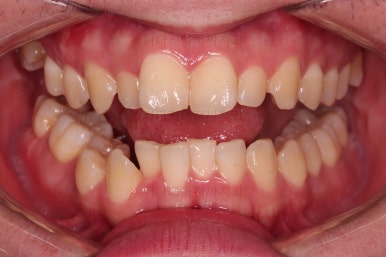

이제 전후 비교를 해볼게요.

1년 7개월 만에 매우 고난이도의 치료를 임플란트 없이 사랑니까지 당겨와서 사용한 만족스러운 치료였습니다.

이상 어금니 결손, 상실치아가 있는 경우 사랑니까지 살려서 앞으로 당겨와서 임플란트 없이 치료를 마루리한 부산교정치과 치료사례였습니다.